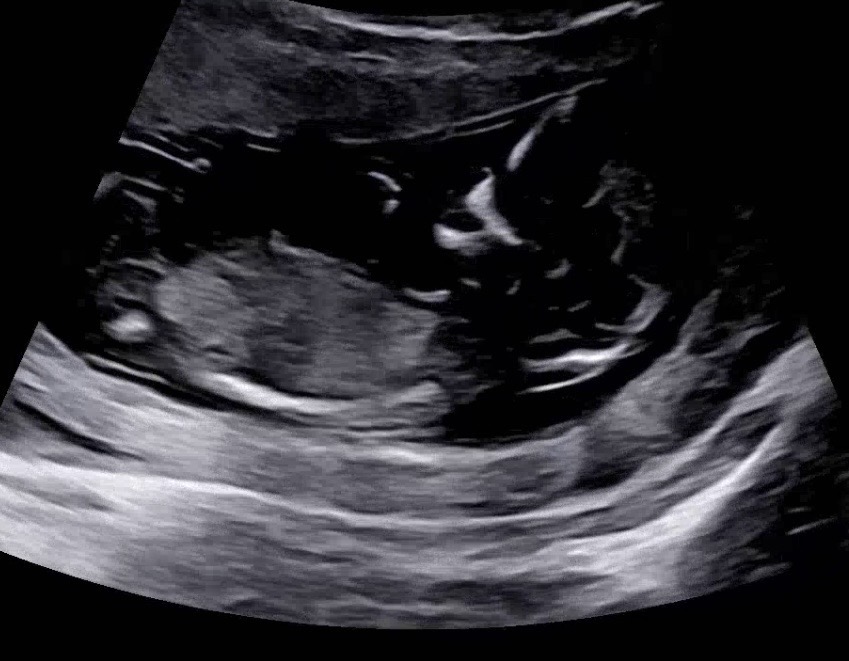

각도법 봐주세용🤩

12주됫어용